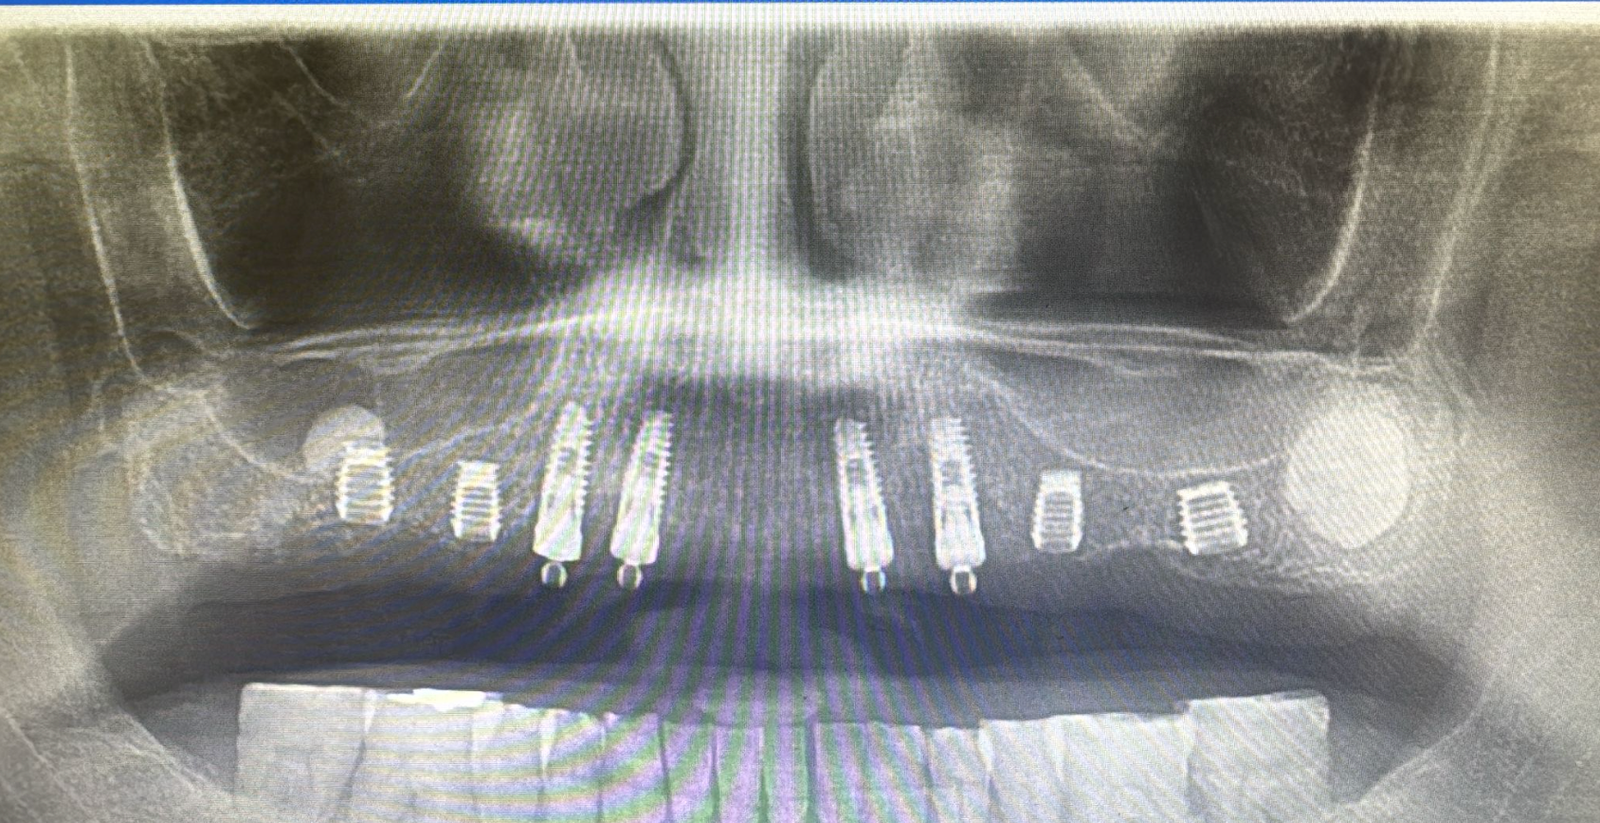

שתלי בייקון - שיקום שיניים מתקדם, מדויק ואסתטי

במרפאת ד”ר בשארה מועאד אנו עובדים עם שתלי Bicon – מערכת שתלים מתקדמת המאפשרת טיפול מדויק, אסתטי ונוח יותר.

יתרונות בולטים:

שתלים קצרים במידת הצורך – לעיתים חוסכים פרוצדורות מורכבות.

חיבור יציב ללא בורג (Locking Taper) – איטום מצוין ותחושת יציבות.

אסתטיקה גבוהה – קו חניכיים טבעי ומראה שן “אמיתי”.

תהליך יעיל ונוח – לרוב פחות התערבויות וזמן החלמה מהיר יותר

שתלים

שתלים דנטליים מחליפים שיניים חסרות בצורה טבעית, יציבה וארוכת טווח

צילומי רנטגן

צילומי רנטגן מתקדמים מאפשרים אבחון מדויק וטיפול מותאם אישית לשמירה על בריאות השיניים